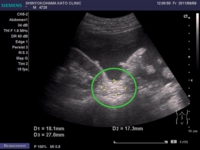

3つ目の症例の患者・Cさん(70歳代・女性)は、頻尿に悩まされることが多くなり、地元の医療機関を受診。神奈川県内の基幹病院において経尿道的膀胱腫瘍切除術を施行した。その結果、膀胱がんの診断を受けた。加えて、がんは右腸骨リンパ節と腹膜へ転移していた(写真2参照)。

写真2 Cさん(70歳代・女性)